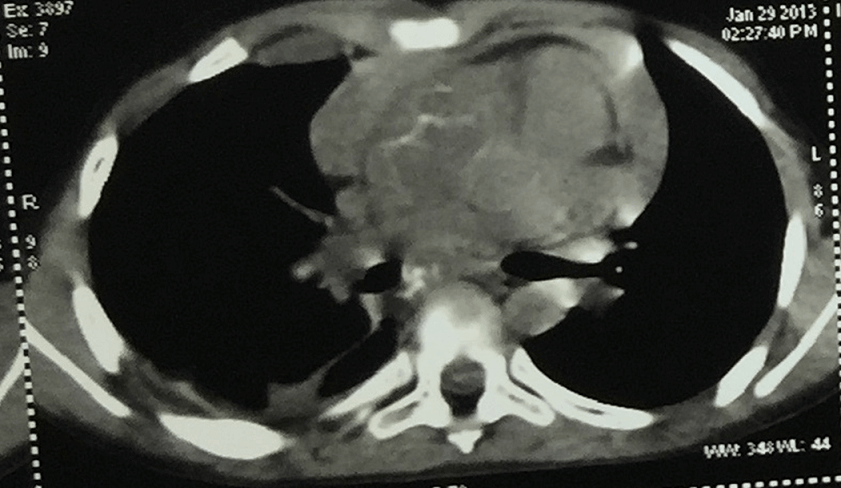

Email: docjagdishkat@gmail.com | | Abstract | | Lymphadenitis is common in primary Tuberculosis (TB) in children and they may be asymptomatic during the non-suppurative lymphadenitis phase. Intrathoracic nodes may compress one of the bronchus leading to atelectasis, lung infection and bronchiectasis or thoracic duct leading to chylous effusion. Other intrathoracic complications include dysphagia, oesophago-mediastinal fistula, tracheo-oesophageal fistula, biliary obstruction and cardiac tamponade. Though mediastinal tubercular lymphadenitis (MTL) is common in developing countries, encasement of aorta by it is extremely rare. We report an eight-year-old girl who presented with non-healing right axillary lymphadenitis, later diagnosed to have MTL and found to have complete aortic encasement. | | | | Keywords | | Mediastinal tubercular lymphadenitis, Aorta encasement, children. | | | | Introduction | | Lymphadenitis is the most common extrapulmonary manifestation of tuberculosis (TB) accounting for 35% of cases.1 It is generally characterized by conglomerates, localized in multiple sites mostly in the right paratracheal, hilar and subcarinal areas, with an inhomogeneous CT enhancement pattern and associated with lung infiltrate in 90% of cases.2 Tuberculous involvement of the ascending aorta is rare, even in a country like India where the burden of TB is enormous, and here we have reported a case of complete encasement of aorta by enlarged MTL which is a first report of an ascending aortic encasement. | | | | Case Report | An 8-year-old girl presented with non-healing right axillary abscess with persistent discharging for 6 months. She was on anti-tuberculous therapy (ATT) for 10 months as she was detected to have primary complex on chest X-ray with positive tuberculin skin test (TST) and fever. After one month of ATT, she developed pericardial effusion with tamponade requiring pericardiocentesis. She also had bilateral pleural effusion and ascites. Pericardial fluid did not grow any organism on culture and TB culture was also negative. Her ATT had been continued and steroids were added. After 5 months of ATT, she developed a right axillary cold abscess. Incision and drainage were done and streptomycin and linezolid were added. The smear showed presence of acid-fast bacilli (AFB). streptomycin was stopped within a month and amikacin and levofloxacin was started which was given for 3 months. Echocardiography was repeated which was normal. On presentation to us, her weight was 16.6 kg, she had pallor and persistent discharging sinus in the right axilla. Blood pressure in upper limbs were 90/40 mm of Hg and that in lower limbs were 120/60 mm of Hg. On systemic examination, she had a systolic murmur at the apex. Other systems were normal. A repeat echocardiography showed solidified collection in the superior mediastinum completing encasing aorta and main pulmonary artery causing constriction with a peak gradient of 23 mm of Hg across it. CT chest showed patchy areas of consolidation in apical segment of right upper lobe and lower lobe and nodular opacities in adjacent lung with localized pleural effusion, pleural thickening on right side and calcified mediastinal and abdominal lymphnodes. (Figure 1) HIV Elisa was negative. On view of clinical suspicion of drug resistant TB, 2nd line ATT consisting of amikacin, moxifloxacin, ethionamide, pas, cycloserine were started along with prednisolone (1 mg/kg/day). Parents were asked to send the pus from the axilla for TB culture, but did not send the same. Child was given total 18 months of this ATT regime (amikacin was given for 6 months). There was no adverse effect to the ATT. Her lymphnodes completely regressed in 1 year and echocardiography was normal after 12 months of this ATT. Her ATT was stopped after 18 months (after CT chest showing complete resolution of the glands). She is on regular follow up and doing well.

Figure 1. CT chest showing mediastinal nodes with right pleural effusion.